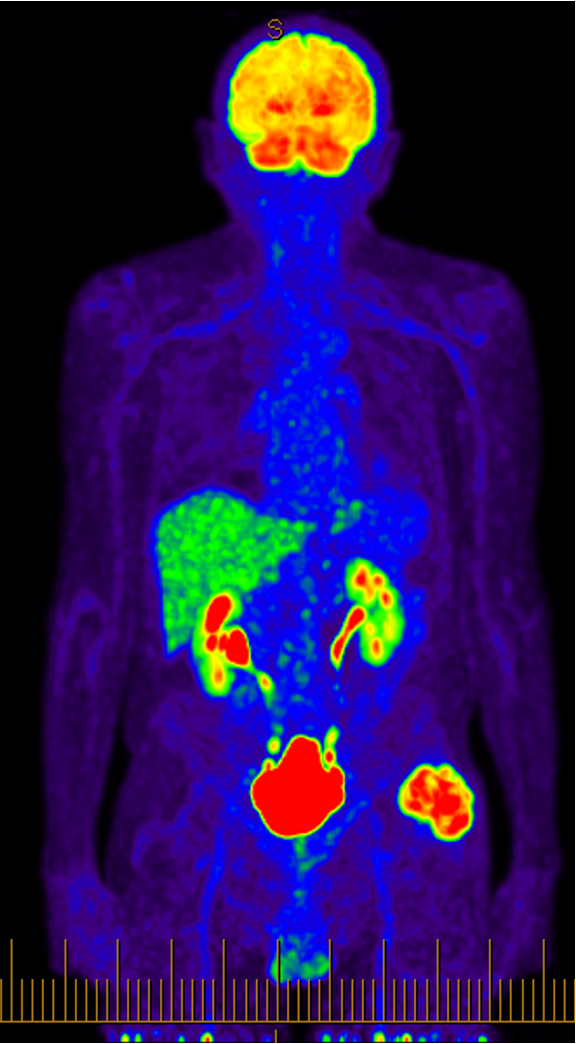

Staging

CXR, CT chest / abdomen

+/- bone scan, PET scan